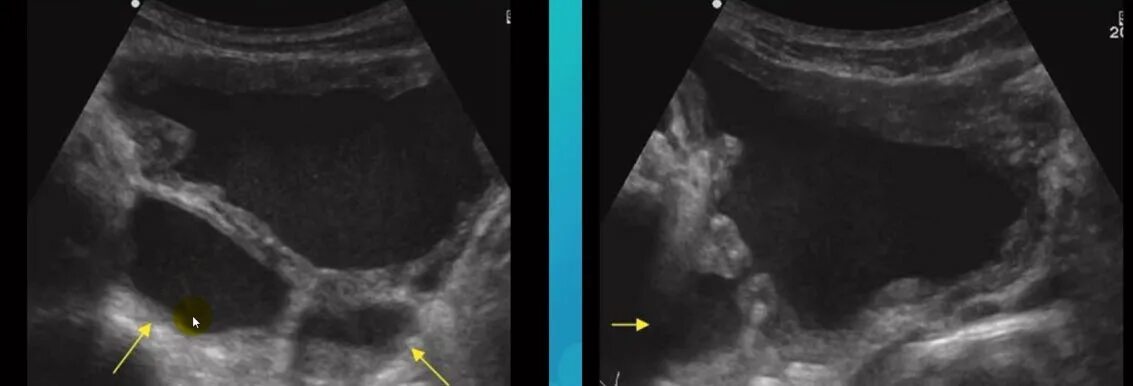

Дивертикул мочевого пузыря что это такое